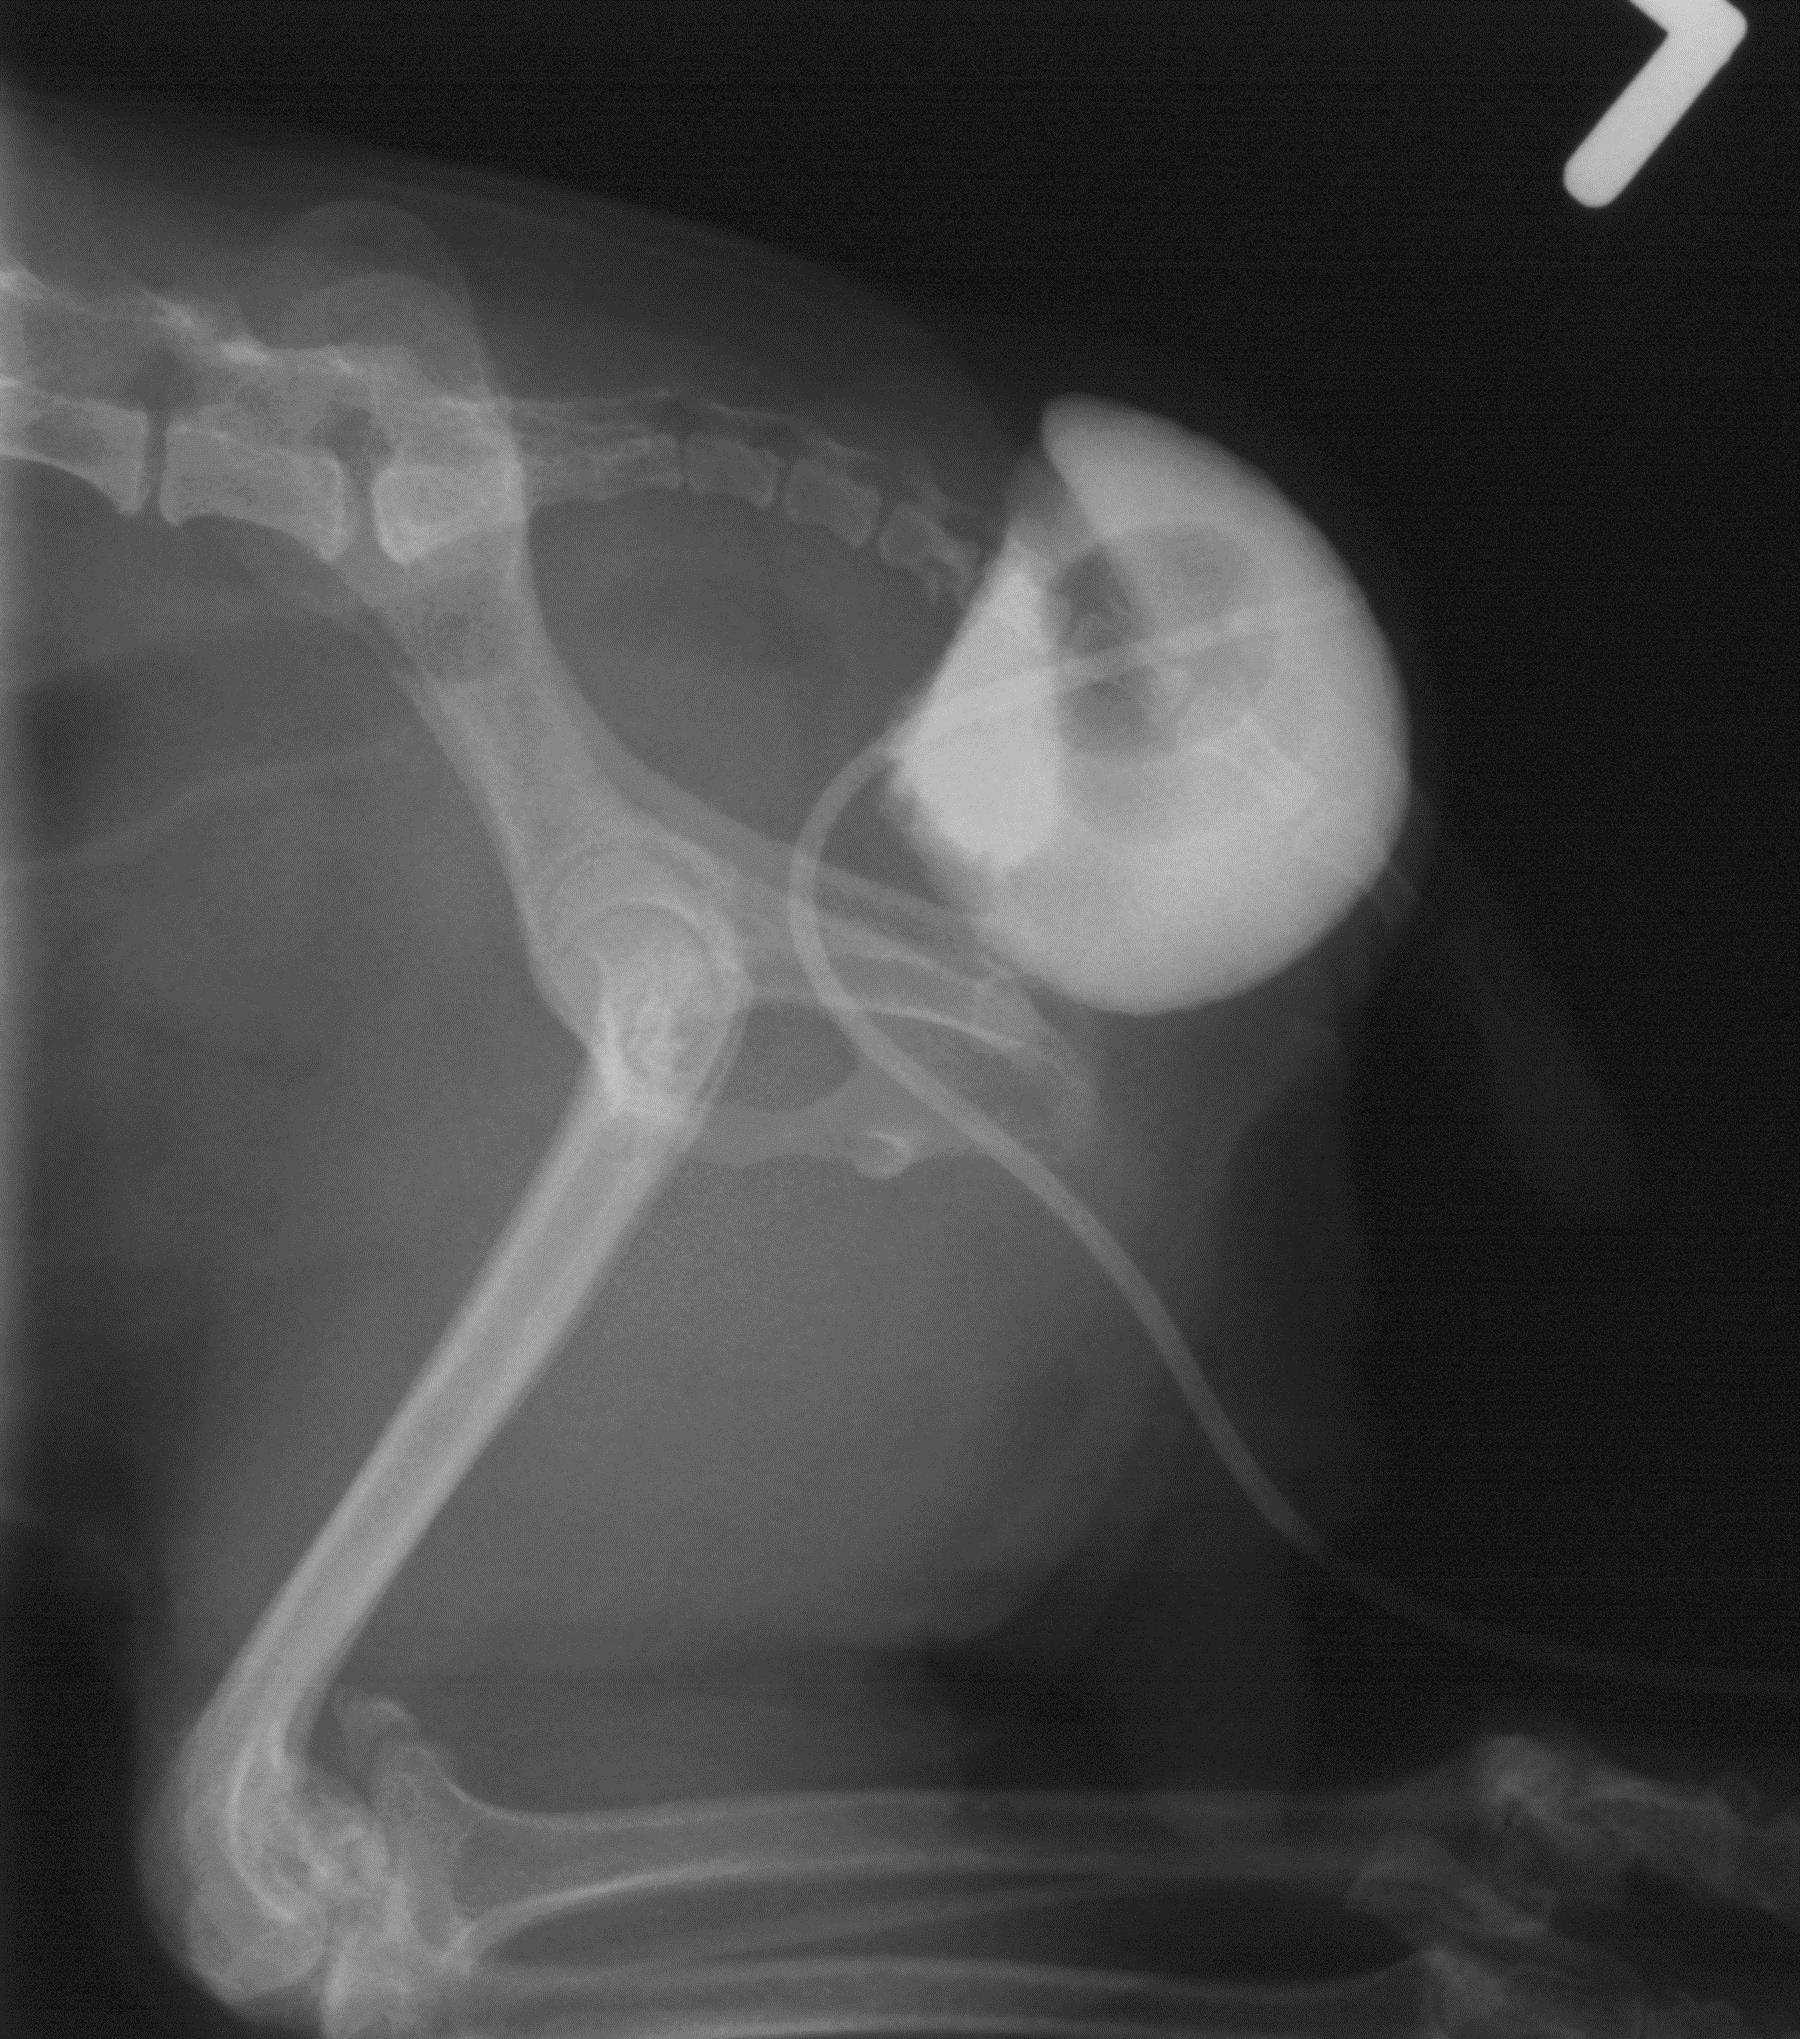

Is your dog experiencing front leg lameness? By Rebecca Wolf, VMD, DACVS-SA Many of the orthopedic problems we diagnose in forelimbs are now treated arthroscopically, meaning smaller incisions, fewer complications, and less postoperative pain. In the shoulder, osteochondrosis dissecans (OCD)…